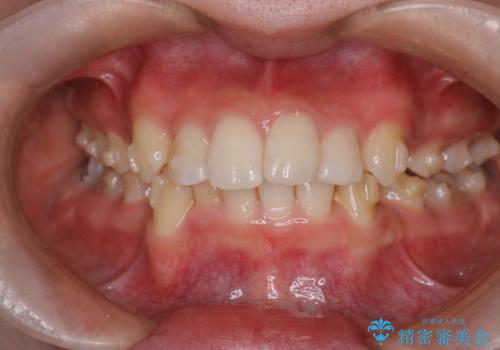

重度の歯のがたつきを、目立たない矯正と抜歯で根本改善

- 前歯から奥歯にかけて歯の重なりが激しい歯のがたつき(重度叢生)を主訴にご来院されました。精密検査の結果、歯が並ぶスペースが大幅に不足しており、歯並びを整え、口元を美しく引っ込めるためには、スペースの確保が必要と診断しました。そこで、上下左右の第一小臼歯(4番目の歯)を計4本抜歯し、そのスペースを利用して歯並び全体を整える抜歯矯正の治療計画を立案。装置には、透明で目立たないインビザラインを採用し、審美性と治療効果の両立を目指しました。

今回の治療では、重度の叢生を改善するため、まず計画通り上下左右4本の小臼歯を抜歯し、歯を並べるための十分なスペースを確保しました。装置には透明で取り外し可能なインビザラインを使用。抜歯によってできたスペースを最大限に活用し、マウスピースを定期的に交換しながら、デコボコを解消しつつ、前歯を効果的に後退させました。

治療の結果、長年の悩みであった重度の歯のがたつきが解消され、口元の突出感も改善。機能的にも安定し、審美的にも美しい、理想的な歯並びを獲得していただけました。